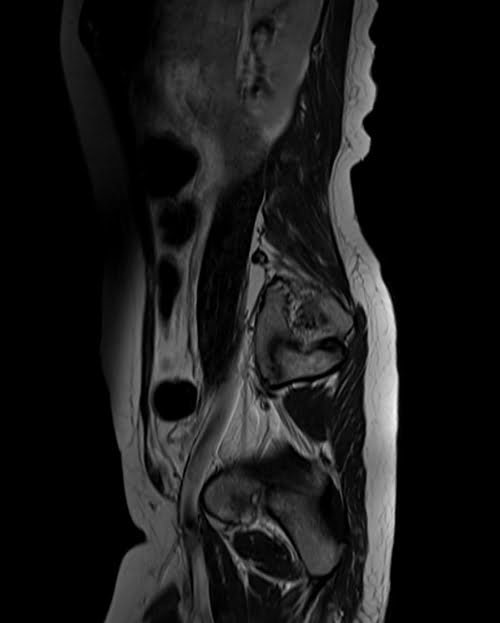

mri lumbosacral plexus sagittal t2 image 2 - MRI